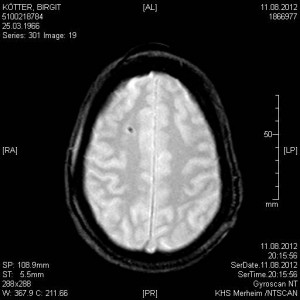

In den Aufnahmen vom 11.08.2012 sind noch eindeutig die Gehirnstrukturen zu erkennen: